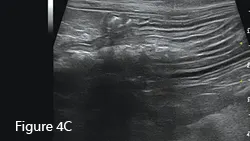

This older cat presented for vomiting; ultrasonography was the first diagnostic modality.

Ultrasound image of an enlarged intestine (arrows) showing large amount of reverberation artifact (arrowheads) caused by luminal gas. This prohibits visualization of the far wall of this loop of bowel. The ultrasound impression was a distended colon.